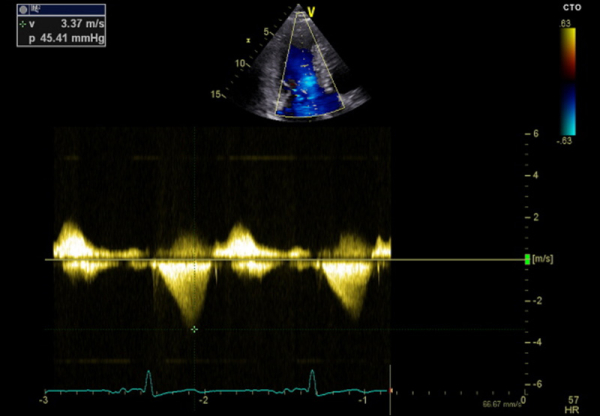

L’échocardiographie d’effort est l’examen de choix qui permet d’évaluer le patient porteur de CMH, à la fois sur le plan fonctionnel, tout en permettant d’objectiver une obstruction absente à l’échocardiographie de repos (latente)(Figure 1) et son mécanisme (Figure 2). Si la prévalence de l’obstruction de repos est de l’ordre de 25 % à 40 % dans la CMH sarcomérique, une obstruction provocable à l’effort physique est observée chez 62 % des autres patients avec CMH symptomatique1.

Figure 1 : Gradient d’obstruction intra-VG provoqué à l’effort.

Si la définition de l’obstruction sous-aortique est retenue devant un gradient maximal du flux Doppler continu > ou égal à 30 mmHg, on considère que, pour qu’elle soit significative en termes de retentissement hémodynamique, le gradient maximal (en Doppler continu) doit être > ou égal à 50 mmHg.